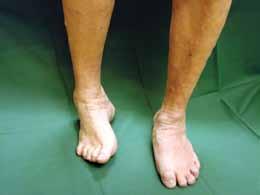

Att bestämma sig för en benamputation är ett svårt beslut för den inblandade och de anhöriga men också ett komplicerat beslut för sjukvårdpersonalen som arbetar med vårdprocessen. Vilken nivå ska man välja? Kommer den valda amputationsnivån att läka? Vilken aktivitetsnivå kan patienten förvänta sig?

När beslutet om amputation är taget så återstår ofta ännu en svår fråga, d.v.s. vilken nivå ska amputationen ske på? I dag finns det inga enkla och/eller säkra metoder som kan förutse läkningspotential på den tänkta amputationsnivån. Oftast blir det en klinisk bedömning av situationen vid operationstillfället som avgör vilken nivå man väljer. Samtidigt vet vi att funktion och nytta med protes hos denna patientgrupp är mycket beroende av om amputationen sker nedanför knäleden. Därför är det viktigt att den som beslutar om nivån är väl informerad om den efterbehandling patienten har möjlighet att få om ett optimalt resultat ska uppnås.

Tidigare har diskussionen handlat mycket om sårläkning på fotnivå och att undvika amputation ovan ankelnivån. I den här artikeln håller vi oss till när detta är oundvikligt, och där valet står mellan att behålla knäleden eller

alternativet, att välja ”säker” läkningsnivå men med risk att bli mer eller mindre rullstolsburen. När amputationen är utförd och läkningen har blivit långdragen eller uteblivit har tidigare det enda alternativet varit amputation på en högre nivå för att säkra sårläkningen.